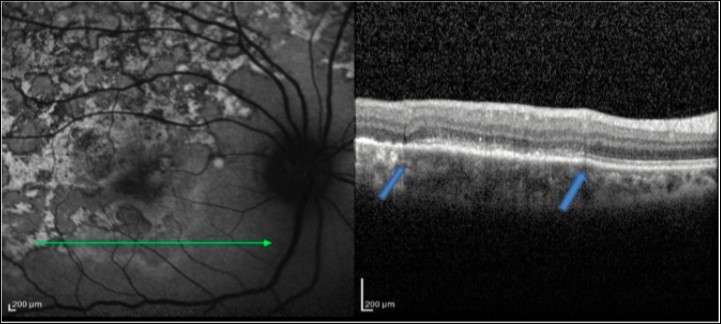

Figure 2.FAF (left) and corresponding eye-tracked SD-OCT image (right) of patient 1 an acute stage of the right eye shows fuzzy area of hyperreflectivity in the outer retinal layers involving the RPE, photoreceptor outer segment tips (POST), photoreceptor inner segment–outer segment (IS/OS) junction, external limiting membrane (ELM), and the outer nuclear layer (ONL) with vitreal and choroidal cells

Figure 3.FAF (left) and corresponding eye-tracked SD-OCT image (right) of patient 1 during healing stage of the right eye shows hyperreflective knobbly elevations of the outer retinal layers. The RPE, the POST, IS/OS junction, and the ELM could not be distinguished. The ONL appeared normal with increased reflectance from the choroidal layers.

Figure 4.FAF (left) and corresponding eye-tracked SD-OCT image (right) of patient 1 healed stage of the left eye shows showed loss of RPE, POST, IS/OS junction, and ELM with increased reflectance from the choroidal layers. absent of the choroidal and intraretinal cells.

1. In an acute lesion of MCS, there was an ill-defined area of increased autofluorescence around the lesion. The SD-OCT passing through the area showed a localized, fuzzy area of hyperreflectivity in the outer retinal layers involving the RPE, photoreceptor outer segment tips (POST), photoreceptor inner segment–outer segment (IS/OS) junction, external limiting membrane (ELM), and the outer nuclear layer (ONL). The lesion was localized external to the outer plexiform layer with a mild distortion of the inner retinal layers. Choroidal and intra retinal layer cells infiltrate with corresponding increase thickness of choroid and inner retinal layers more obvious in EDI-OCT. There was no increased backscattering from the inner choroid.

2. As the lesions started to heal, they became well defined and acquired a thin border of hypoautofluorescence while remaining predominant hyperautofluorescent centrally. The SD-OCT scan through the hyperautofluorescent area showed disappearance of the hyperreflective fuzzy areas that were replaced by irregular, hyperreflective knobbly elevations of the outer retinal layers. The RPE, the POST, IS/OS junction, and the ELM could not be distinguished. The ONL appeared normal. At this stage, there was an increased reflectance from the choroidal layers due to attenuating RPE–photoreceptor complex.

3. As the lesions healed further over the next 3–6 months, they appeared stippled with predominantly hypoautofluorescence. The SD-OCT scan showed loss of RPE, POST, IS/OS junction, and ELM with absent of the choroidal and intraretinal cells. The increased reflectance from the choroid persisted.